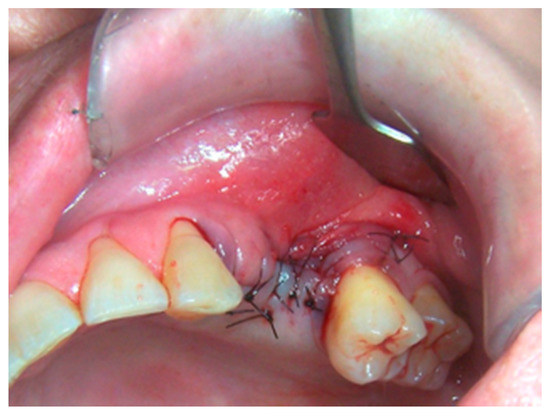

2. Materials and Methods

3. Results

4. Discussion